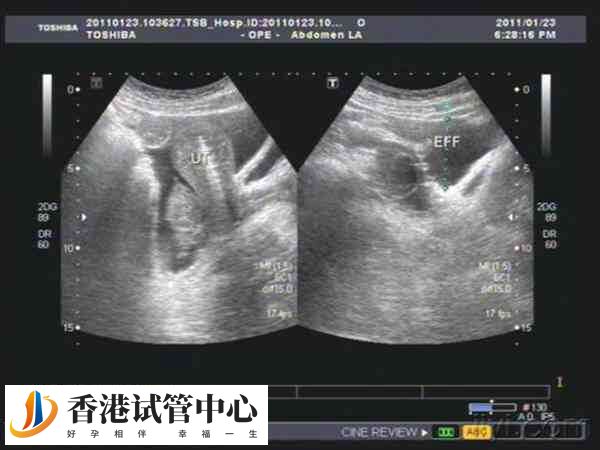

做試管促排28個(gè)卵泡的患者,雖然更多的卵泡可以增加成功的機(jī)會,但是否能提高試管嬰兒成功率,通常取決于多個(gè)因素,包括女性的年齡、身體狀況以及卵子質(zhì)量等多個(gè)因素。如果取出的是高質(zhì)量的卵子,且精子活力好,那么可提高受精率和胚胎質(zhì)量,從而增加成功率,反之則可能會降低試管助孕幾率,具體不可一概而論。

很多做試管嬰兒的姐妹為了獲得更多卵子,會在試管嬰兒前期投入大量的時(shí)間和精力,有甚者更是提出了增大促排卵藥量的方法,但盲目追求取卵數(shù)量是不科學(xué)的,比如有的患者直接促排26個(gè)卵泡,至于患者促排28個(gè)卵泡做試管成功率高不高,還要從以下幾個(gè)方面判斷。

促排28個(gè)卵泡做試管成功率高不高,通常與患者的年齡有關(guān),如果患者身體狀況較好,子宮環(huán)境較好,內(nèi)膜厚度適宜,醫(yī)生的技術(shù)也是比較好的,那么就有可能在取出28個(gè)卵泡后,配成很多個(gè)優(yōu)質(zhì)胚胎,這時(shí)移植成功率相對較高。

影響試管嬰兒成功率的因素還包括年齡,畢竟在試管嬰兒治療過程中,女性會因?yàn)殡S著年齡增長,卵巢功能逐漸下降,卵子的質(zhì)量和數(shù)量也會受到影響。如果年齡大,那么即使促排28個(gè)卵,也會降低移植成功率。

患者促排28個(gè)卵泡做試管時(shí),如果質(zhì)量不佳,或者培育出的胚胎質(zhì)量差,都可能導(dǎo)致試管失敗。反之如果促排的28個(gè)卵泡質(zhì)量比較好,那么培養(yǎng)的胚胎質(zhì)量也比較好,這時(shí)移植成功率也就相對較高。